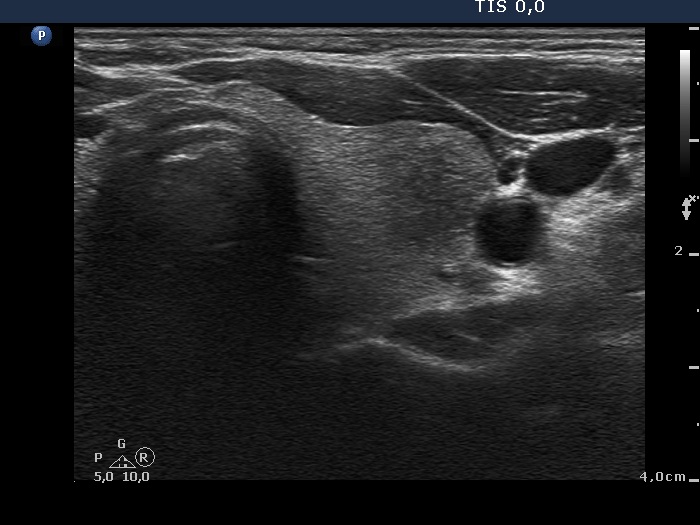

Follow-up 2 months after the first visit (3rd row of images):

Clinical presentation: Within 24 hours of the administration of 32 mg methylprednisolone, the neck complaints and subfebrility had stopped. When the patient reduced the dose to 8 mg daily for 2 weeks as suggested, the left lobe became sensitive. This tenderness has now been significantly reduced, but still persisted at times.

Palpation: The left lobe was tender on palpation.

Laboratory tests: TSH 1.62 mIU/L, FT4 9.97 pM/L, CRP 0.1 mg/L.

Ultrasonography: The right lobe decreased in size as did the extent of hypoechogenic areas in this lobe. The left lobe remained unchanged.

Suggestion: Discontinuation of steroid therapy. TSH in three months.

Follow-up 6 months after the first visit (3rd row of images):

Clinical presentation: The patient had no complaints.

Palpation: no abnormality.

Laboratory tests: TSH 2.06 mIU/L, FT4 13.3 pM/L, CRP 0.3 mg/L.

Ultrasonography: The pattern of the entire thyroid became almost completely normal. Only small hypoechoic areas were observed.

Suggestion: TSH in six months, in the event of pregnancy at once.

Follow-up 5 years later (3rd row of images):

Clinical presentation: Six months after the previous visit the patient became pregnant. The TSH was 5.91 mIU/L at the 5th gestational weeks. Replacement therapy was given which was ceased after delivery. The patient was free of complaints and the TSH was in the normal range, even during a next pregnancy 2 years later. Recently, a few weeks after COVID-19 infection, she noticed tenderness in the right side of the neck.

Laboratory tests: TSH 1.72 mIU/L, CRP 3.5 mg/L.

Ultrasonography: The thyroid was intact.